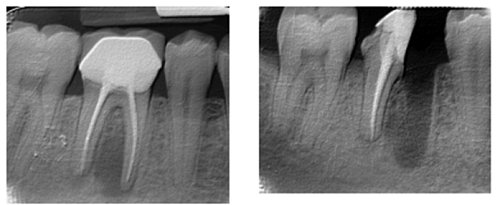

Na poniższym zdjęciu rentgenowskim (lewym) widać dwa korzenie zęba trzonowego. Lewy korzeń wygląda zdrowo. Natomiast prawy korzeń  przedstawia duże zaciemnienie wokół wierzchołka które świadczy o niewyleczonej infekcji. Na zdjęciu z prawej strony widać ten sam ząb po odcięciu chorego korzenia.